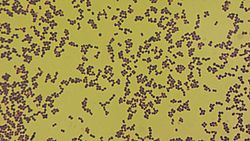

| Microscopy of Aerococcus urinae with gram stain, showing gram positive cocci.[1] | |

Aerococcus urinae is a Gram- positive, catalase- negative coccus that frequently grows in clusters. Belonging to the genus Aerococcus.

What makes it tricky is that under a microscope, A. urinae shows up as small Gram-positive cocci in clusters or pairs—similar to other bugs we see all the time. On blood agar, it can be alpha-hemolytic or even non-hemolytic, making it even harder to distinguish. In many labs, it was historically brushed off as a contaminant or misidentified entirely.